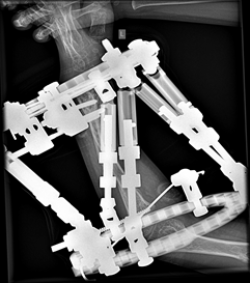

Olier’s disease

The images show a case of Olier’s disease which had a short and deformed forearm. He underwent surgical intervention by Dr. Zenios with the use of external osteosynthesis.

Pre-operative

External osteosynthesis